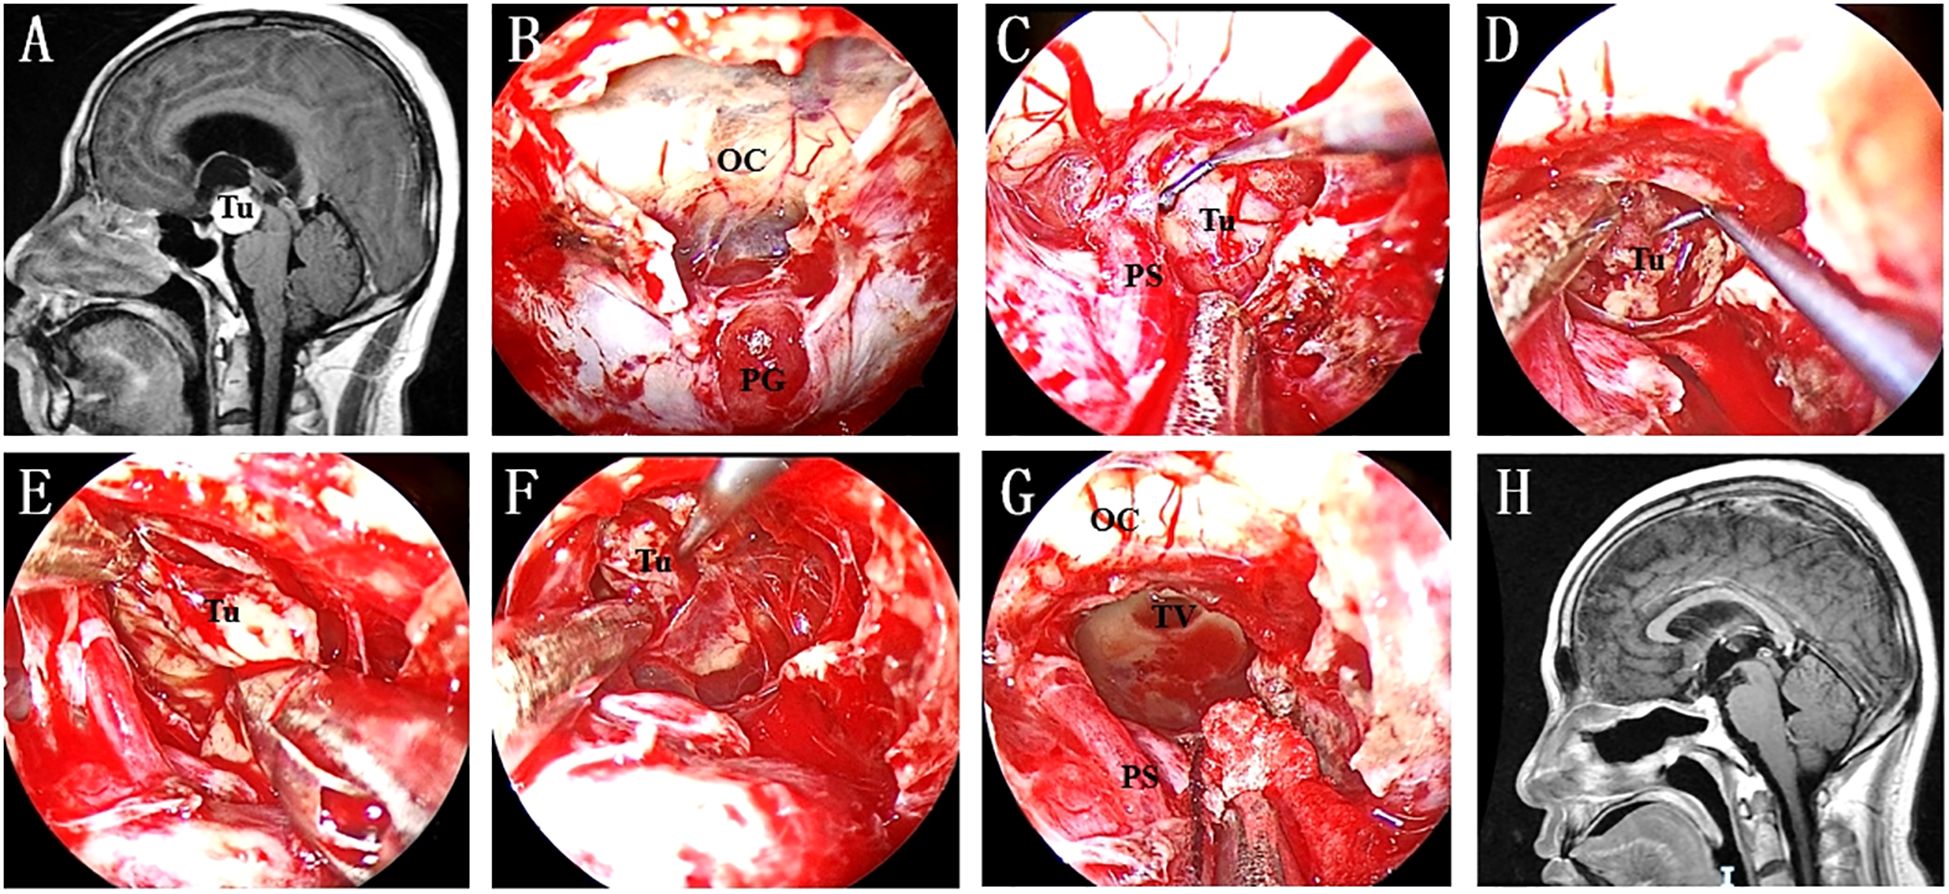

Although the specific techniques vary, endoscopic resection of retroinfundibular lesions is considered a microsurgical operation Figure 4. Ring curettes and suction are the most commonly used tools for intratumoral debulking. Following this first step, extracapsular dissection was carried out at the interface, if it could be identified, between the tumour capsule and arachnoid planes. Under direct visualization of neurovascular structures, including the PG/PS, SHA and OC, the arachnoid bands covering the tumour capsule are sharply and carefully separated, avoiding injuring the small neurovascular perforators. We strongly recommend discontinuing the procedure if these arachnoid bands cannot be sharply resected. For lesions without a macroscopic encapsule, negative margins can be ensured based on tumour texture and surgical experience.

Figure 4. (A) Preoperative MR image showing a lesion in the retroinfundibular area. (B) A “Y”-shaped dural incision was made to expose the PG and optic chiasma. (C) The lesion was exposed after intradural PGT and clival dura opening. (D) Intratumoral debulking was performed as the first step to ensure extensive tumour resection. (E) The medial interface was identified after enough tumour debulking. (F) Inferior extracapsular dissection was continued to achieve radical tumour resection. (G) The TV was opened after the tumour was completely resected. (H) No residual tumour or recurrence was found on postoperative MRI. Tu, tumour; OC, optic chiasma; PG, pituitary gland; PS, pituitary stalk; TV, third ventricle.